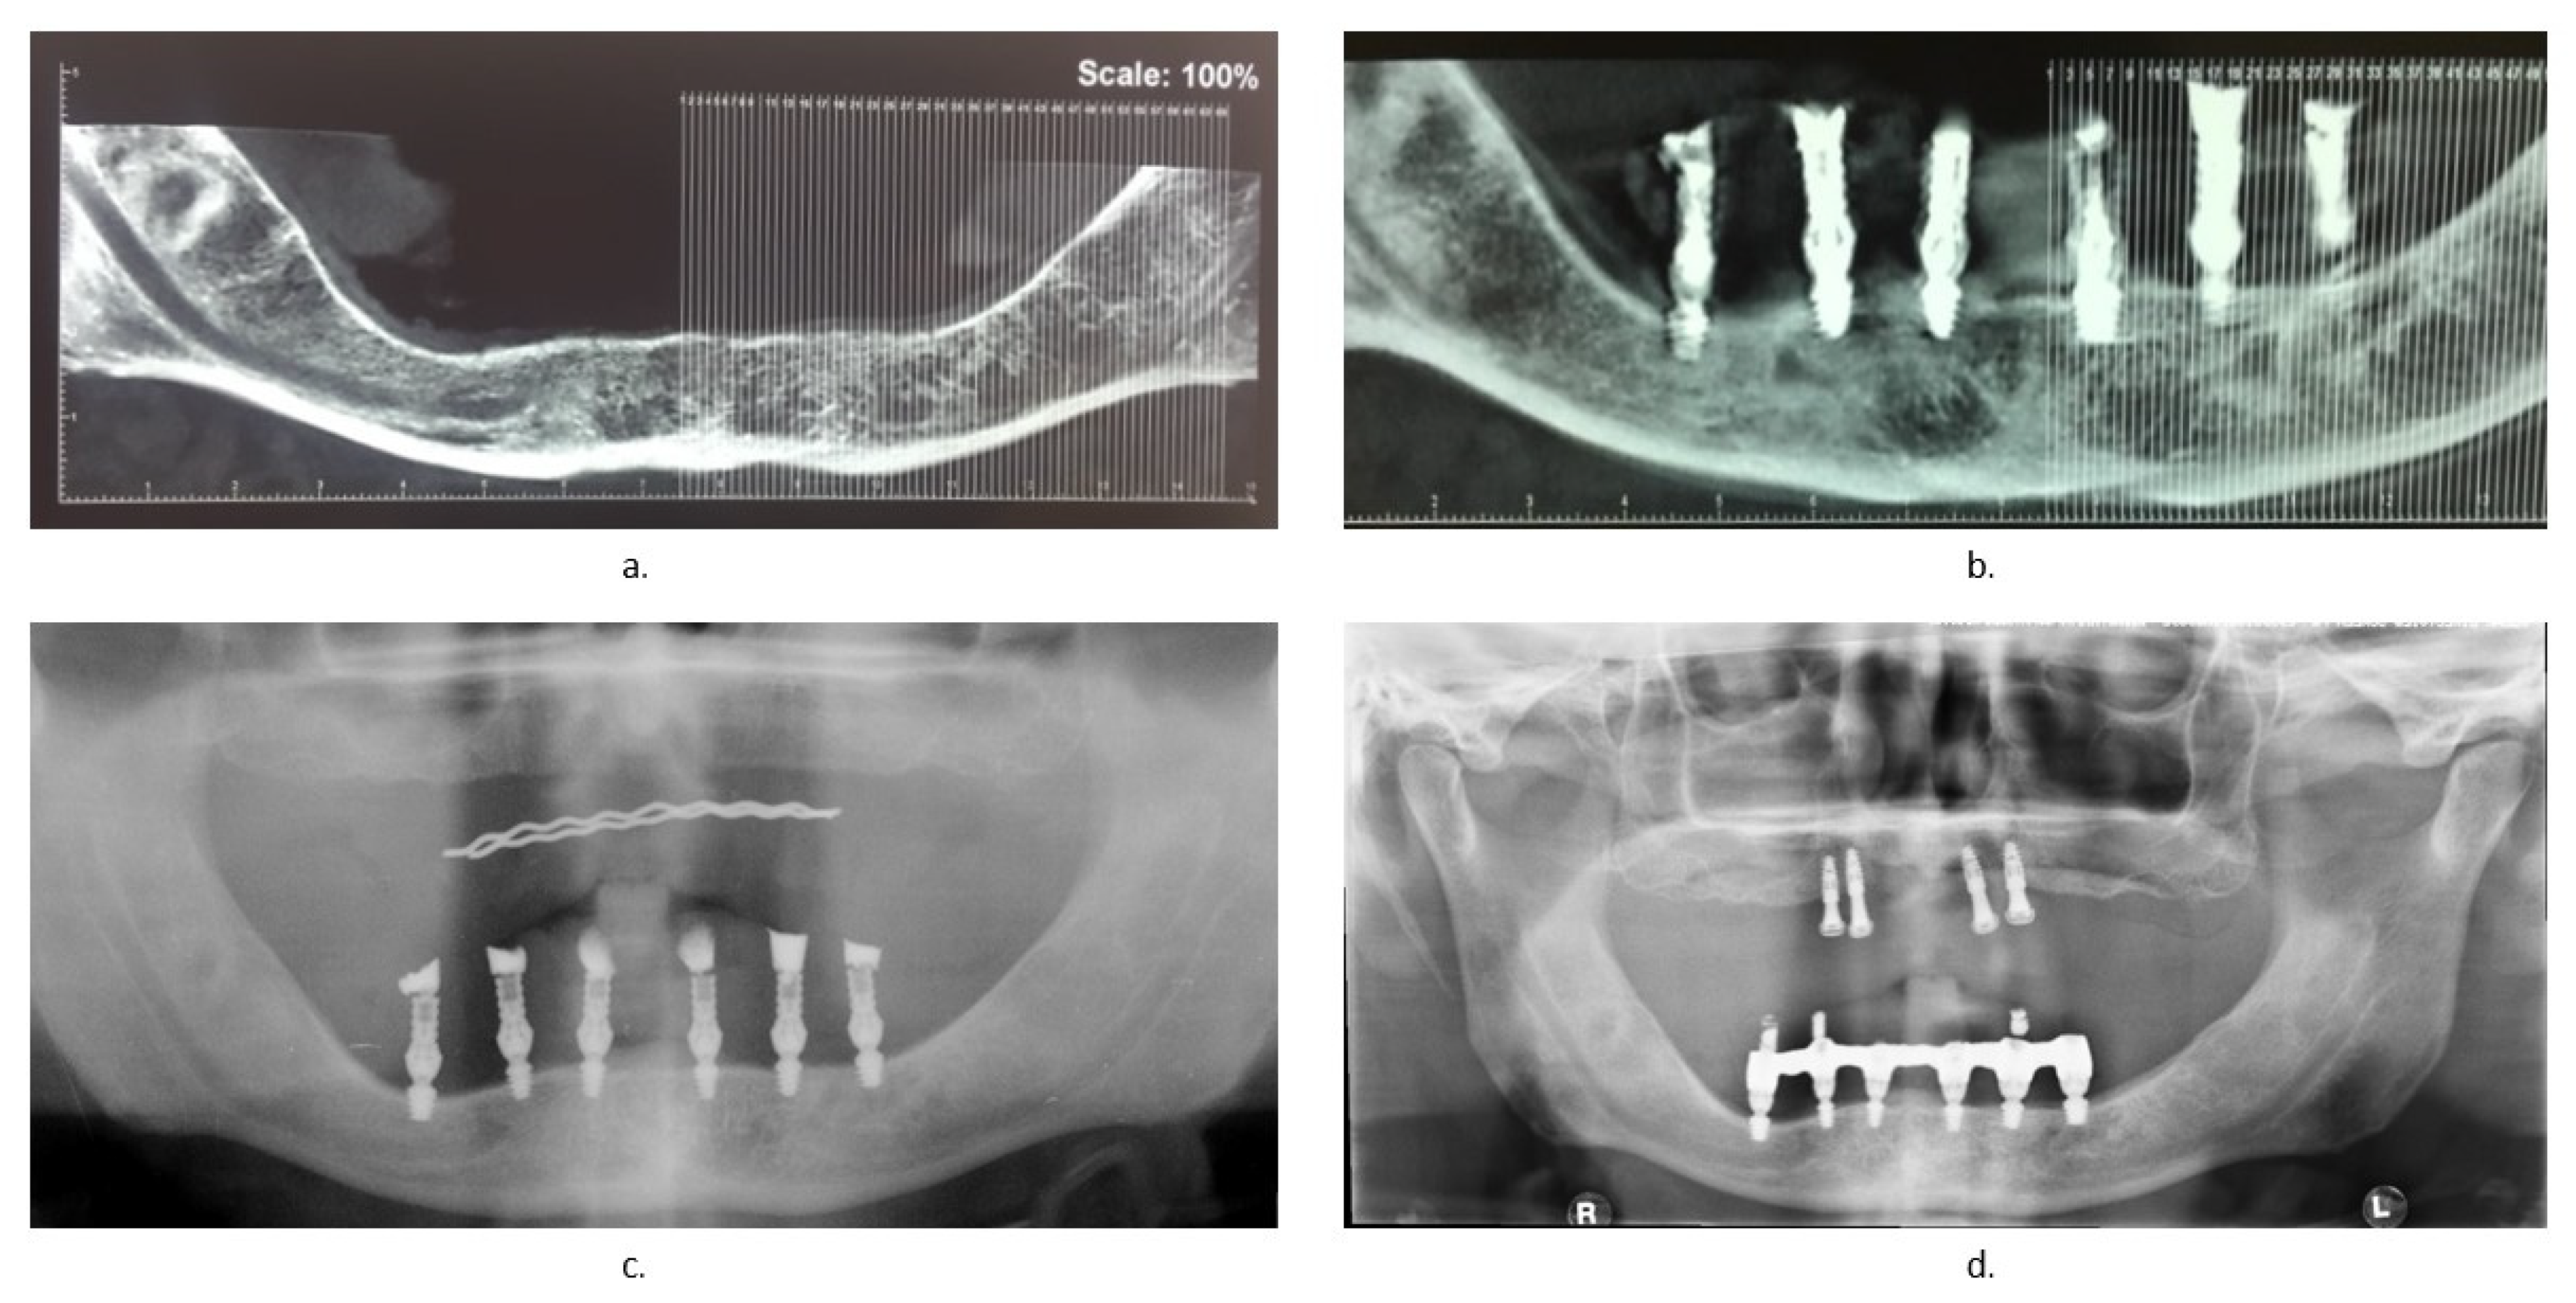

Seven days after surgery, a clinical examination of the patient was performed, in which the healing status of the mucosa and the implant stability were analyzed and the sutures were removed. After 4 months, a cone beam was performed to assess whether the bone healing status had no problems (Figure 4b), before proceeding with the realization of the final prosthesis with a screwed bar. An OPG (Orthopantomography) was carried out 1 year (Figure 4c) and an X-ray OPG was carried out 3 years (Figure 4d) after the realization of the definitive prosthesis.

Figure 4.

Radiographic checks: (a) cone beam before surgery; (b) cone beam 4 months after surgery; (c) OPG (Orthopantomography)1 year later; (d) OPG 3 years later.